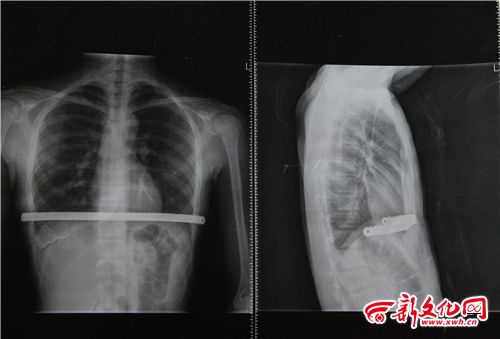

小博術(shù)后拍的CT片 本組圖片 新文化報(bào) 史磊 攝

家人懷疑小博的高燒與今年二月做的手術(shù)有關(guān),因?yàn)榛加新┒沸兀〔┳鍪中g(shù)在體內(nèi)植入了鋼板。家人帶小博到北京的醫(yī)院檢查,檢查結(jié)果顯示各項(xiàng)指標(biāo)都正常,不能確定小博高燒與之前的手術(shù)有關(guān)。